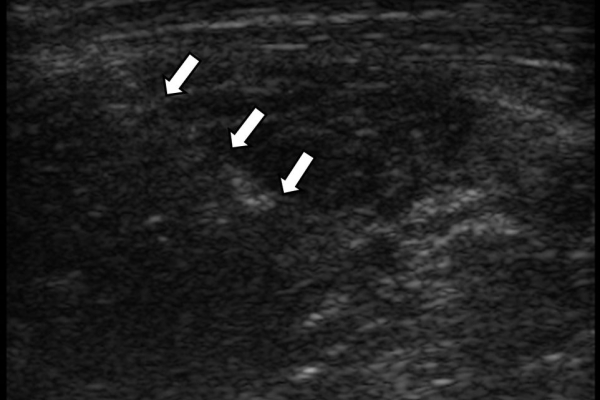

Οι κατευθυνόμενες εγχύσεις σε αθλητικές κακώσειςαποσκοπούν στη μείωση του πόνου, την ενίσχυση της αποτελεσματικότητας της φυσικοθεραπείας και την επιτάχυνση της διαδικασίας επούλωσης για την πιο γρήγορη επάνοδο του αθλητή στις αθλητικές του δραστηριότητες. Η πιο διαδεδομένη έγχυση αποτελεί η έγχυση PRP.Ανήκει σε μια σύγχρονη θεραπευτική μέθοδο γνωστή ως Ορθοβιολογική θεραπεία και βασίζεται την ικανότητα του οργανισμού να θεραπεύεται με τα δικά του αποκλειστικά θεραπευτικά μέσα χωρίς να υπάρξει χρήση φαρμάκων.Το PRP (Platelet Rich Plasma)-πλάσμα πλούσιο σε αιμοπετάλια- σήμερα αποτελεί μια θεραπευτική μέθοδο πρώτης γραμμής με σχετικά μεγάλη επιτυχία για την επούλωση τραυματισμένων τενόντων, μυών και εκφυλιστικών παθησεων όπως οστεοαρθρίτιδα.Η εφαρμογή του περιλαμβάνει μία ευρεία ποικιλία από παθήσεις όπως:

- Συνδεσμικές κακώσεις

Η έγχυση γίνεται πάντοτε με την βοήθεια υπερηχογραφικού ελέγχου ώστε να είμαστε απόλυτα σίγουροι για το σημείο έγχυσης τοπικά.